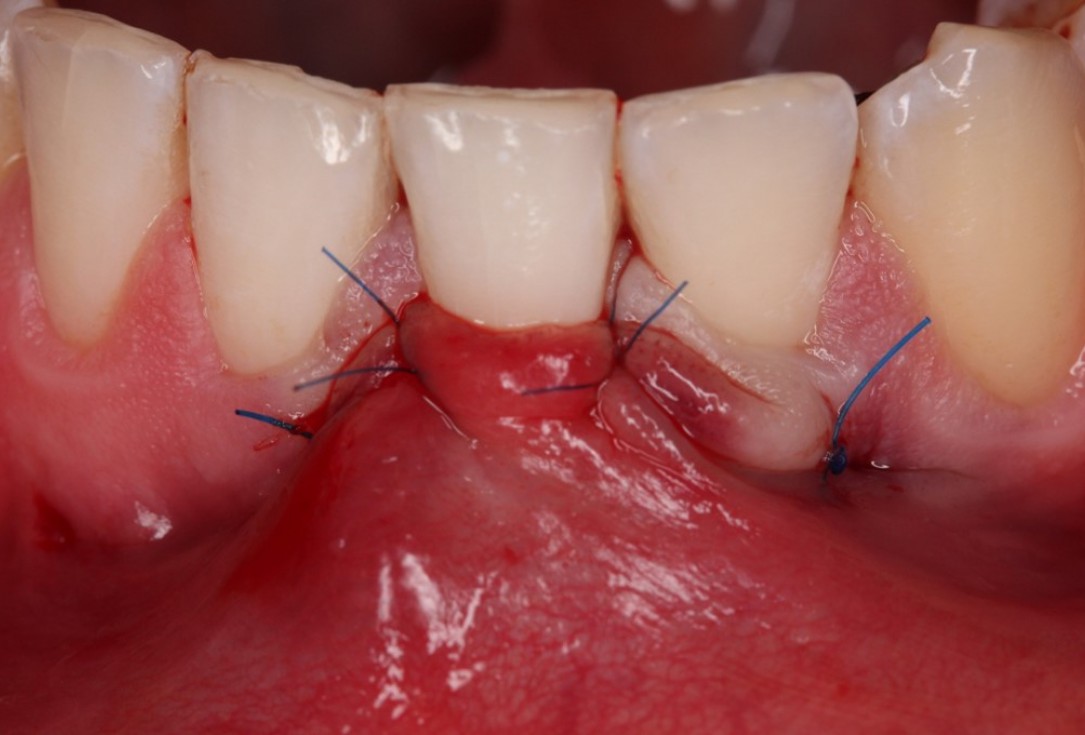

05/06 - Suturing.Isolated gingival recession treated with the modified coronally advanced tunnel in conjunction with Straumann® Emdogain® and autologous CTG - Dr. R. Cosgarea